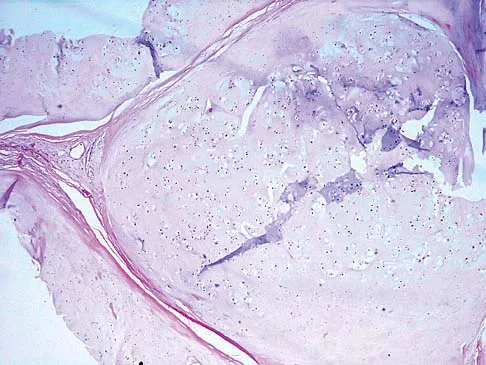

A 69-year-old man has a painful slow-growing lesion of the distal phalanx of his thumb. History reveals that he has had chronic osteomyelitis of the thumb for the past 12 years. The radiograph and biopsy specimens are seen in Figures 9a through 9c. Treatment should consist of

Explanation

The diagnosis is squamous cell carcinoma. The radiograph shows a destructive lesion, and the histologic slides demonstrate squamous cells invading bone. The preferred treatment for squamous cell carcinoma is wide resection; however, in this location a wide margin can be achieved only with amputation. Overall survival in patients with squamous cell carcinoma secondary to chronic osteomyelitis is not significantly worse than that expected for age-matched controls. Dell PC: Hand, in Simon MA, Springfield D (eds): Surgery for Bone and Soft Tissue Tumors. Philadelphia, PA, Lippincott-Raven, 1998, pp 405-420.